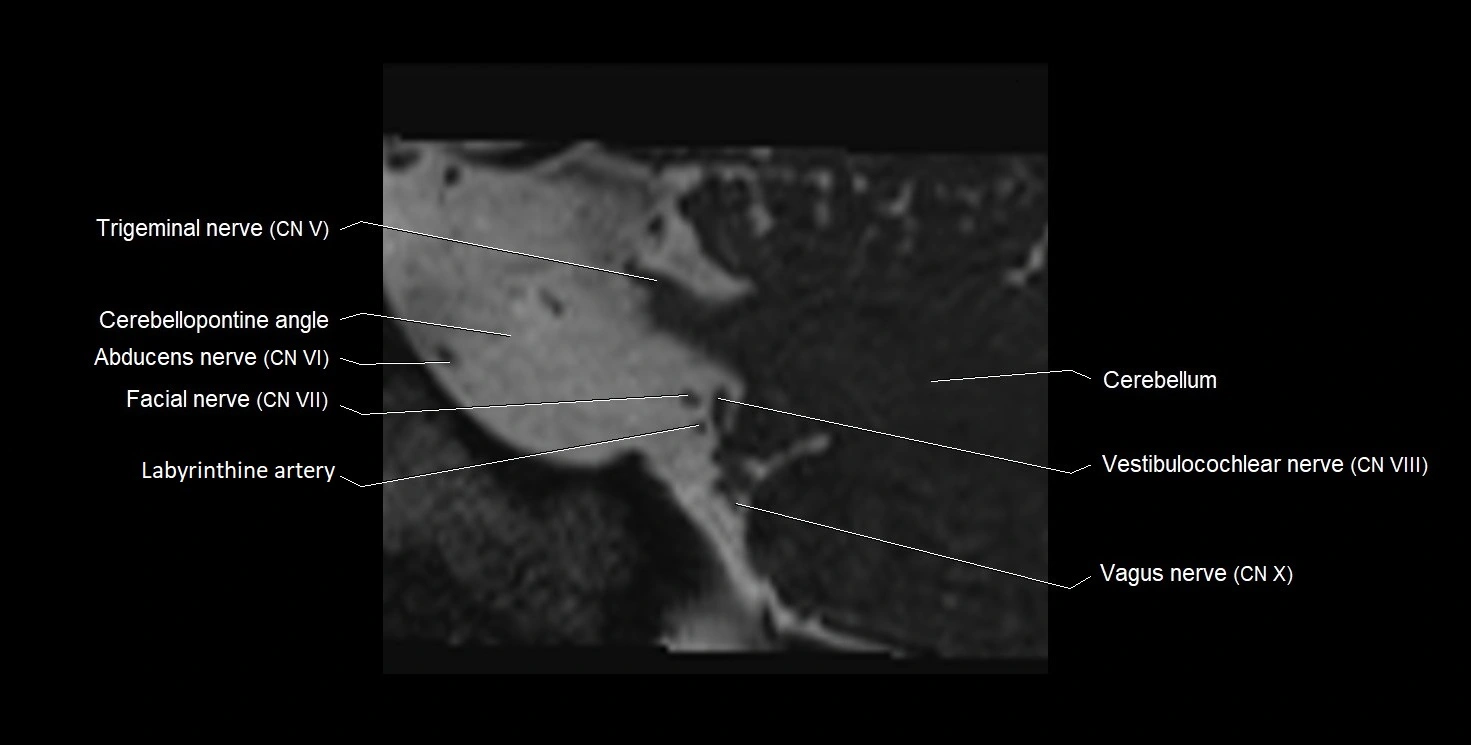

MRI Appearance

• The abducens nerve is a small, thin, linear structure

• Best visualized on high-resolution T2-weighted 3D MRI sequences (e.g., FIESTA or CISS)

• Seen as a hypointense (dark) line running from the brainstem at the pontomedullary junction, traversing the prepontine cistern, and entering Dorello’s canal under the petrosphenoidal ligament, then into the cavernous sinus, and finally the orbit

• May be challenging to visualize in standard MRI due to its small size

• Pathology may be inferred by absence, displacement, or enhancement of the nerve